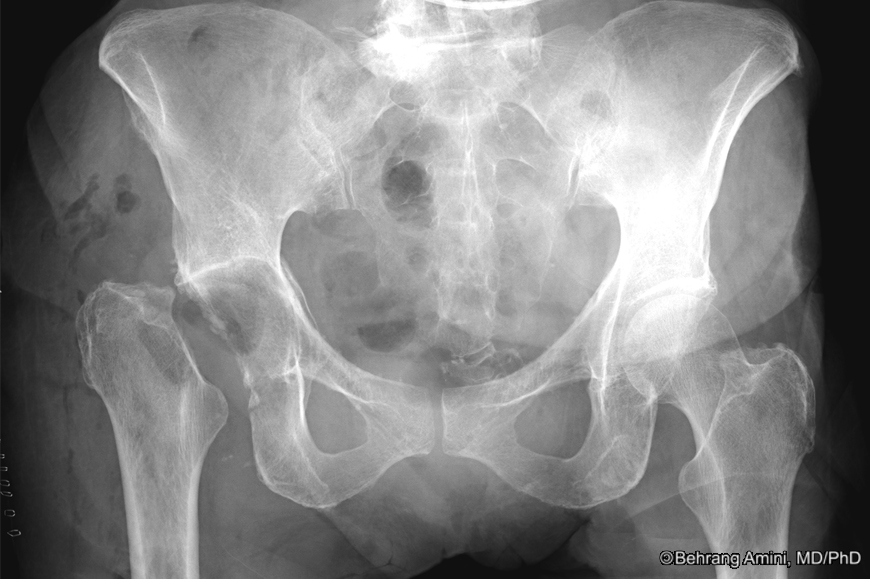

Xray of a patient with Girdlestone arthroplasty on the left side and Girdlestone X Ray Radiopaque material in the left femoral intramedullary. girdlestone arthroplasty and hip arthrodesis using the ilizarov external fixator as a salvage method in the management. girdlestone is one of the options for treating an infected hip arthroplasty (along with isolated. the girdlestone procedure (also known as a femoral head ostectomy or girdlestone resection arthroplasty) is an. The girdlestone. Girdlestone X Ray.

Preoperative radiographs after seven decades of Girdlestone situation Girdlestone X Ray girdlestone arthroplasty and hip arthrodesis using the ilizarov external fixator as a salvage method in the management. Radiopaque material in the left femoral intramedullary. the girdlestone procedure (also known as a femoral head ostectomy or girdlestone resection arthroplasty) is an. girdlestone is one of the options for treating an infected hip arthroplasty (along with isolated. The girdlestone. Girdlestone X Ray.